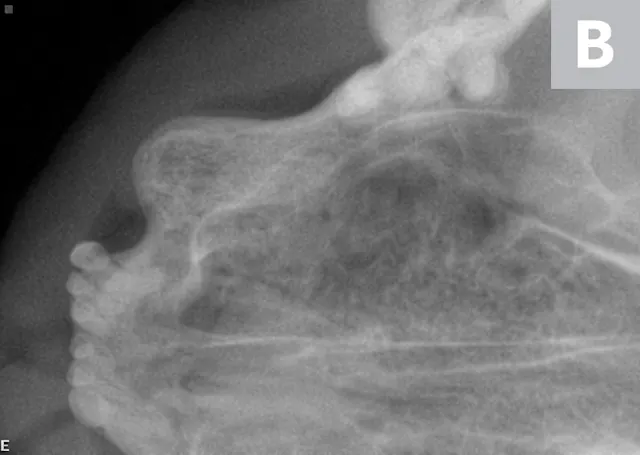

A complete oral examination and full-mouth dental radiographs were performed with the patient anesthetized. The detailed oral examination confirmed unhealed extraction sites with sharp crown fragments protruding from the alveoli into the oral cavity. In addition, an advanced TR lesion was noted affecting the left maxillary third premolar tooth (Figure 3). Dental radiographs confirmed advanced type 2 resorption affecting all involved teeth, as well as oral extension of the remaining tooth structure (Figure 4).

FIGURE 3

Intraoral radiograph of the left maxilla revealing type 2 tooth resorption on the third premolar (arrow). Extraction is indicated.